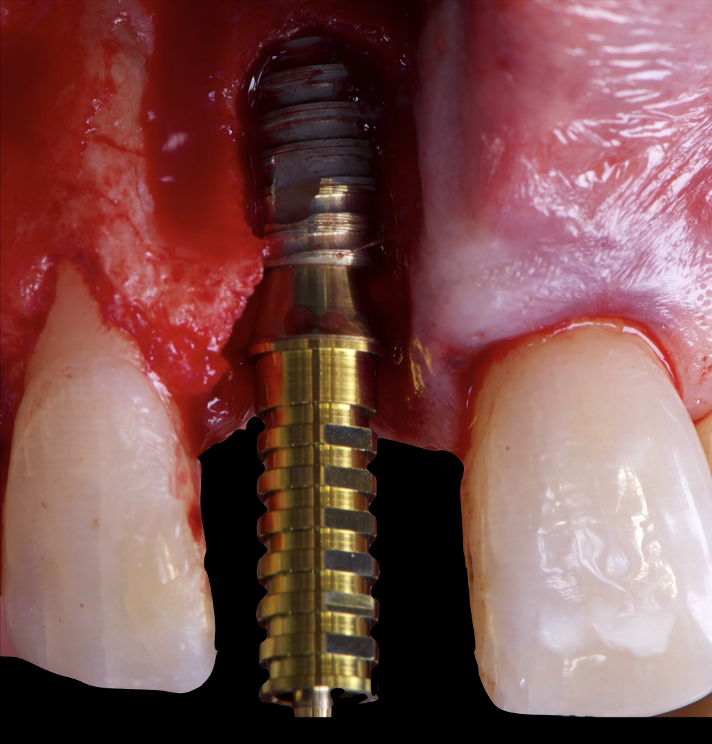

On the same day as the surgery, an immediate-load provisional crown was delivered. This restoration was fabricated in acrylic resin and screw-retained on the implant, following the “one abutment one time” principle. The provisional crown was carefully adjusted to avoid occlusal loading while supporting the peri-implant soft tissue architecture during the healing phase.

The provisional not only satisfied the patient’s functional and esthetic demands but also played a key role in shaping the emergence profile and conditioning the gingival margin. By providing a provisional solution immediately, the patient was able to leave the clinic with a natural-looking smile, avoiding any psychological or social impact associated with tooth loss in the anterior maxilla.